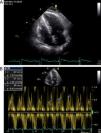

Realizou um cateterismo cardíaco esquerdo e direito, tendo sido excluídas lesões angiograficamente significativas nas artérias coronárias e confirmado o diagnóstico de pericardite constritiva no estudo hemodinâmico (com as típicas curvas de pressão ventricular em dip-and-plateau e equalização das pressões telediastólicas). Na aortografia foi documentada dilatação da aorta torácica descendente. Para melhor caracterização da aorta, foi realizado uma angio-TC de tórax, que revelou um volumoso aneurisma saculiforme, parcialmente trombosado, com origem na aorta torácica descendente, imediatamente distal à emergência da artéria subclávia esquerda, com 87 x 61mm de diâmetro (Figura 2); não se observou calcificação do pericárdio.